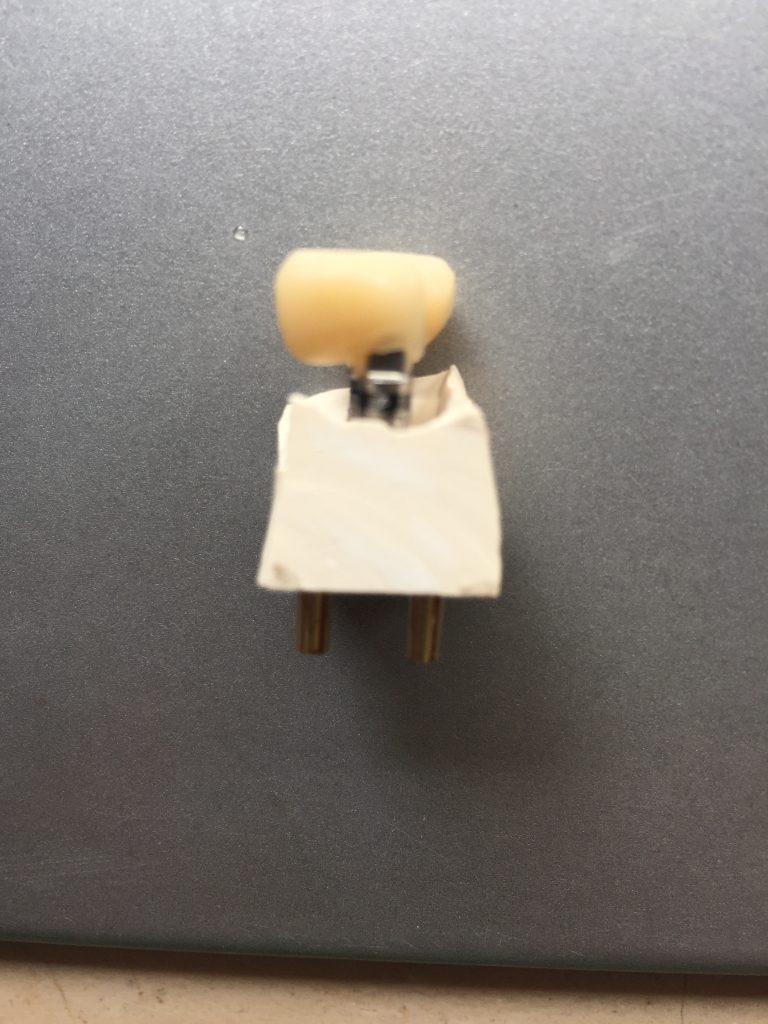

Autores: PRÓLOGO Asimismo, desde el punto de vista pedagógico, el profesional nobel en la materia tiene a su alcance la posibilidad de corregir cualquier posición implantaría en el ordenador, planear los provisionales y plasmarlos en la bio réplica antes de tocar al paciente a operar. Todos estos razonamientos nos llevan a presentar un caso de condiciones muy favorables para poner en práctica estos métodos como primer acercamiento a una Odontología Digital de alta calidad, con medios informáticos, que ya están presentes en la profesión de hoy en día, y será la protagonista única del futuro. Por otro lado, después de numerosos estudios que nos llevan a plantear el “gap” entre implante y pilar(abuttment), como principal responsable de la periimplantitis dado que la microbiota presente en el mismo es imposible de limpiar y en su presencia la cortical ósea reacciona reabsorbiéndose, nos ha llevado a utilizar implantes monobloc ya que los ejes implantarios y protéticos coincidían, y nos permitían su uso. Además, el circonio, ha mostrado a la luz de estudios muy recientes, una preservación y adhesión de los tejidos blandos superiores al titanio, tanto en su tratamiento de superficie de la rosca como a nivel gingival. DESARROLLO Paciente varón de 68 años, con antecedentes de radio/quimioterapia cinco años antes, con Rehabilitación Oral de los cuatro cuadrantes, con una Oclusión Mutuamente Compartida conservada, (REF.8) la que fracasa en el cuadrante 4, 19 años después. El mismo presentaba un puente de porcelana sobre circonio con pilares en 44 y 47, reemplazando el edentulismo de 45 y 46. Se produce la fractura del PM del 44, y ante una endodoncia antigua y corta, se decide implantar las zonas edéntulas, conservando temporariamente los pilares, hasta producida la oseointegración, para entonces también exodonciar el 44. DIAGNÓSTICO Tomamos impresiones del maxilar antagonista, Arco Facial Estático y realizamos montaje del mismo mediante la sistemática ARTEX. Producimos la relajación del músculo Pterigoideo Externo, para obtener la ORC (Oclusión en Relación Céntrica) mediante el método de Laminillas de Long, basado en el concepto de INERVACIÓN RECÍPROCA. Esto nos permitirá montar el maxilar inferior, tanto en su forma de: La primera para practicar la cirugía guiada y comprobar su eficacia, y el modelo de yeso para ser escaneado y confeccionar la GUÍA QUIRÚRGICA. La Biorréplica la obtenemos transformando los archivos DICOM que nos da el CBCT en archivos STL, y a partir de ellos, mediante una tecnología de PROTOTIPADO RÁPIDO, la obtención de un objeto físico en 3D a través de la aglutinación selectiva de una sucesión de capas de polvo. Procedemos a montar la biorrèplica y el modelo de yeso del caso. Podemos verificar la exactitud de las medidas del hueso residual en la bio réplica y compararlas con el scanner. Arrojando un resultado de 8,5 mm de cortical externa a cortical externa. Pudiendo también medir la distancia hasta el dentario. y comparar gracias a la ventana lateral de la biorréplica Dándonos 22mm de distancia. Con lo cual deducimos que implantes de 4,1mm por 12 mm serán perfectamente rodeados de hueso. Medimos también la distancia desde oclusal del antagonista, hasta el hueso desnudo. Lo mismo que, mediante la utilización de la guía radiológica, con un material radiolúcido colocado en gingival de la misma, podemos medir la altura de la encía. Con lo cual podemos calcular la altura del pilar. Es entonces cuando con el programa COC Diagnostix se realiza la programación final: Obteniendo no solo la ubicación, largo, ancho y ángulo de los implantes sino también los provisionales mediante CAD CAM. Ya entonces podemos hacer la práctica quirúrgica en la bio réplica, mediante la guía quirúrgica, instalando los implantes de prueba que no serán los de circonio, ya que la casa no cuenta con ellos, pero si otros de las mismas dimensiones. TRATAMIENTO Entramos ya en la cirugía propiamente dicha. Antisepsia de la zona a operar y zonas anexas. Comprobación del perfecto ajuste e inmovilidad de la G.Q. en boca durante la cirugía. Marcado de la encía y perforación de la cortical. Visión a través de la Guía de la mínima intervención anterior. Comprobación sin Guía. Incisión mínima mesio distal, para apartar y conservar encía queratinizada. Secuencia de drills, perforando a profundidad requerida Observación del Mínimo Trauma Implantes Strauman de Zirconio Monoblock en blíster y montádo en contrángulo reductor. Instalación controlando torque con contrángulo reductor. Comprobación clínica. Comprobación Radiográfica y con Guía. Toma de impresiones, y armado de modelos con técnicas de pasividad protética. Montaje. Resultado de las provisionales ejecutadas por CAD CAM Al no estar conformes con el resultado decidimos desechar dichas provisorias y optar por repetirlas. Nuevas provisorias realizadas mediante encerado convencional. Estado de los tejidos blandos. Provisorias en boca. Oclusión de Estímulo Inmediato. Ref.10: Carga inmediata .Alberto y Diego Bechelli. Comprobación mediante CBCT post operatorio Componentes del equipo (En la próxima presentación, mostraremos las coronas definitivas de porcelana sobre circonio, y la desoclusión provocada por una OCLUSIÓN MUTUAMENTE COMPARTIDA, sobre estos implantes y otros seis mas) REFERENCIAS

FIG: 14-15-16-17-18-19-20

Fig. 14

Fig. 15

Fig. 16

Fig. 17

Fig. 18

Fig. 19

Fig. 20

Fig 82-83-84

Fig.85-86

Fig. 87

Fig. 88

Fig.89

Fig. 90-91

Fig.92